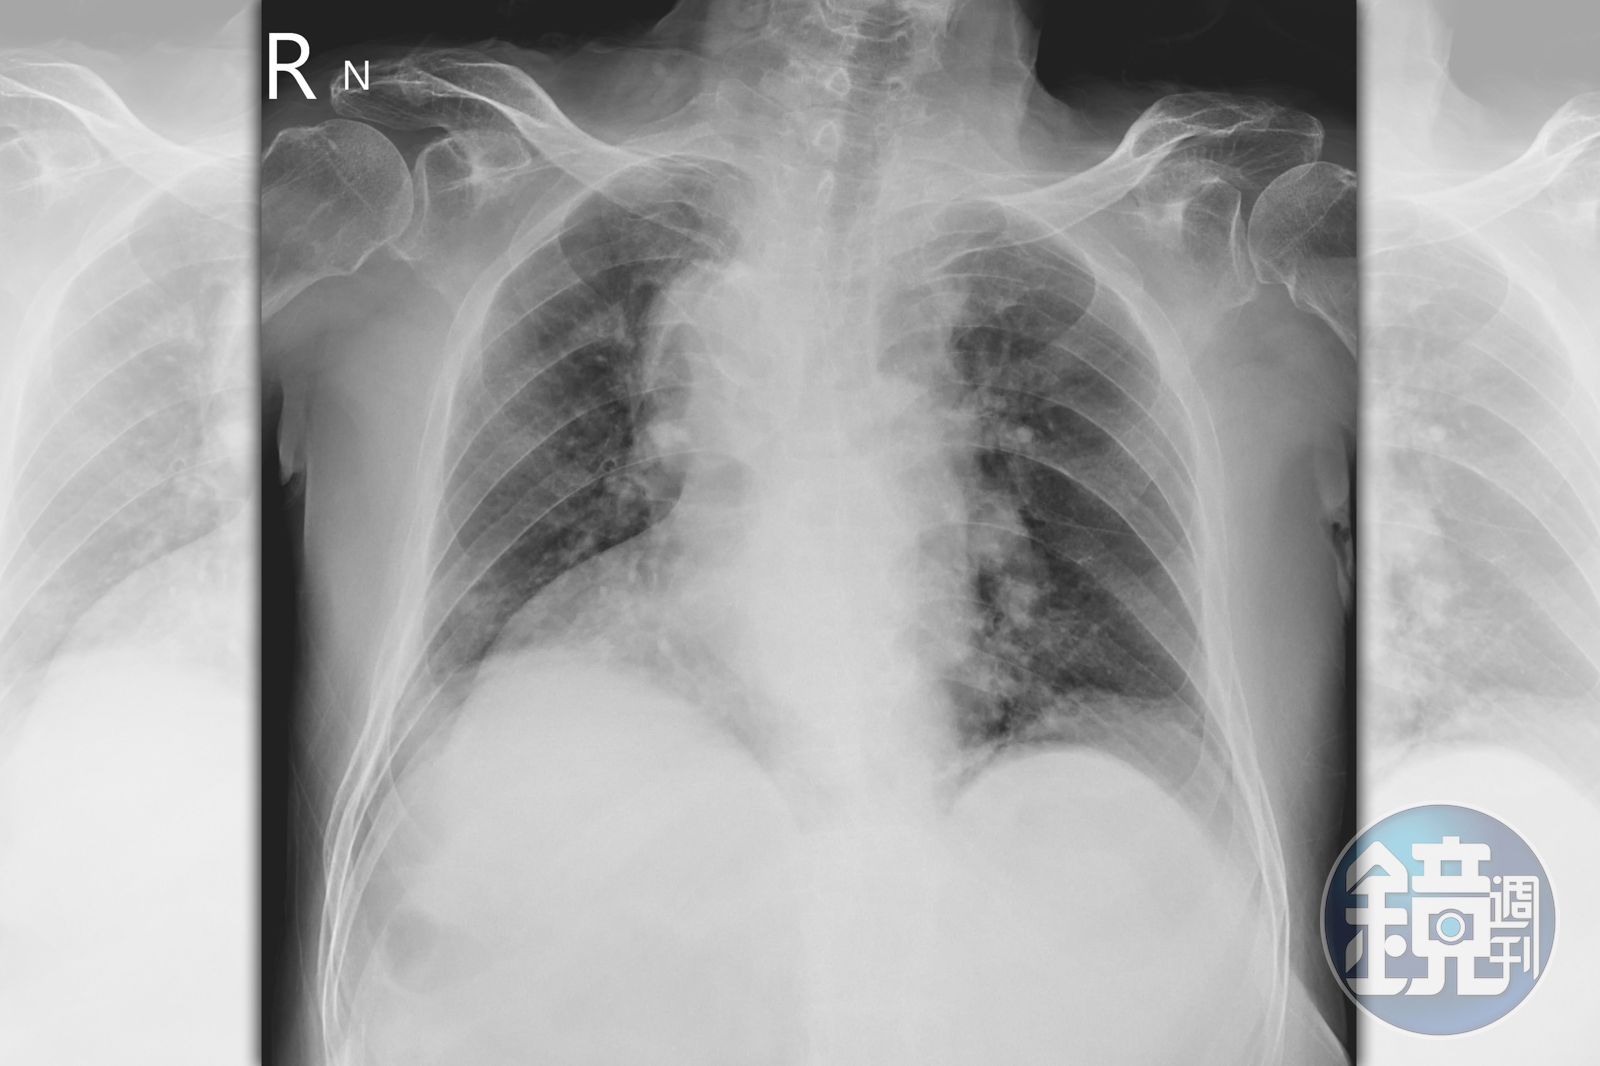

北市聯醫陽明院區胸腔科主治醫師蘇一峰日前在臉書po文分享,遇到一名70歲患者擁有萬中無一的身體構造,他替老翁拍攝胸腔X光後驚呼「哇!伯伯,你的身體很特別喔!」並告知老翁「你的心臟在右邊,而肝臟在左邊,全身的的內臟器官走向左右相反喔!有人跟你說過嗎?」沒想到患者笑說「沒有人跟我說過,今天才知道」。

蘇一峰解釋,「器官轉位(situs inversus):發生機率小於萬分之一,有另外一種類似的型態是只有心臟左右相反(Dextrocardia)右位心(Dextrocardia):發生的比率則比較常見一點,全身器官左右正常,但是只有心臟是左右顛倒!」

蘇一峰補充表示,「器官轉位的病人,有些合併其他疾病,會引起呼吸道的問題,氣管擴張症和鼻竇炎和不孕!台灣現在醫藥發達,器官轉位的問題常常小時候就會被發現,病人在照胸腔X光片中被發現」。